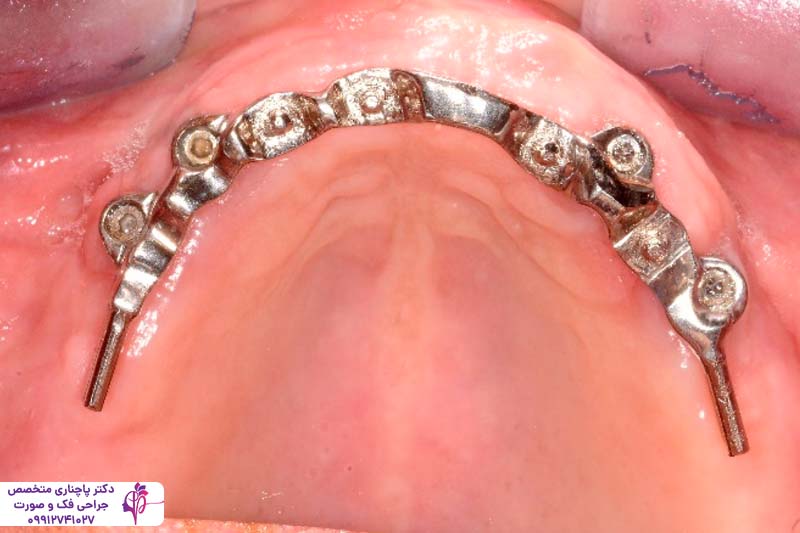

- اوردنچر با بار فلزی یا bar-retained

در آن یک میله فلزی روی ایمپلنتها قرار میگیرد و پروتز با کلیپس به آن متصل میشود. این مدلها ثبات خوبی دارند و راحت نیرو را توزیع میکنند ولی نصب آنها راحت نیست و در نتیجه تمیز کردن آنها سختتر میشود.